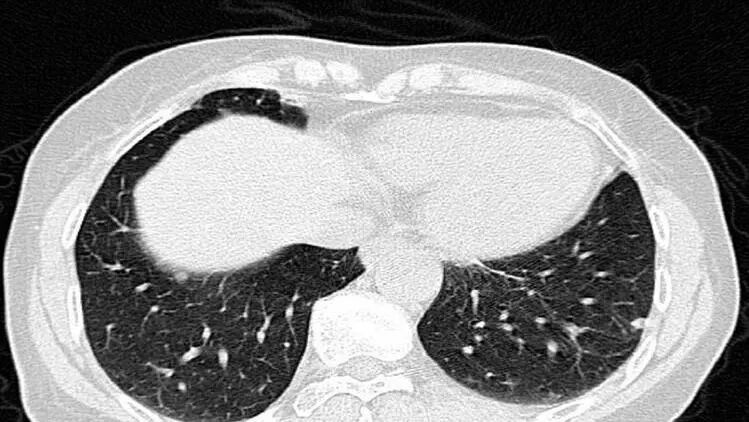

别被“CT”吓到,其实它比很多检查都简单。一个无创、无痛的高分辨率成像技术,能立体还原你冠状动脉的全貌。

做完后,医生可以直观看到血管内有没有斑块,斑块大小、位置、是否钙化,以及有没有引发血管狭窄。